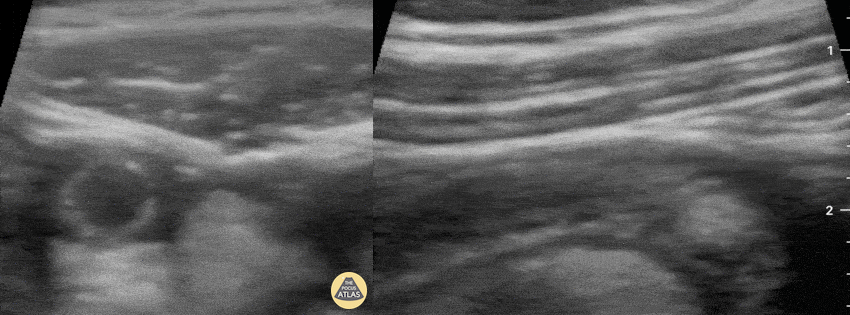

A 5-year-old patient with no relevant medical history was brought to the ED the previous day complaining of fever and mild abdominal pain. Due to a lack of specific clinical findings, he was treated with antipyretics and swabbed for COVID-19, which was negative. The following day, on its second visit to the ED, the child's fever persisted and had substantial abdominal pain that did not respond to first-line treatment, requiring subsequent use of ketamine. Physical examination was non-specific. POCUS of the RLQ immediately revealed acute appendicitis, as shown in this series of clips. Notice here on the left, the circular appendix in transverse view which is not deformed by compression with the probe; also can appreciate an abundance of peri-appendicular free fluid in the surroundings. Fanning the probe reveals an intraluminal fecalith with posterior acoustic shadowing. On the right is a longitudinal view also revealing an intraluminal fecalith. The patient was transferred to the regional referral hospital, and successfully underwent surgery which confirmed gangrenous appendicitis. Dr. Felipe Urriola P. Emergency Unit, Puerto Aysen Hospital. Chilean Patagonia.